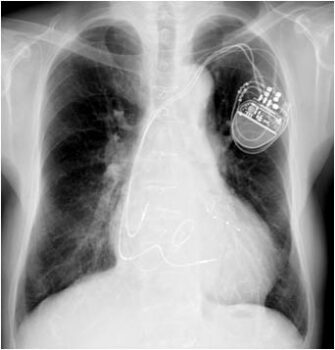

心電図、心エコー、胸部レントゲン、血液検査、ペースメーカーチェックのフルコースでした。

すべての検査を終え、ペースメーカーチェックをしてもらっていた時、どのような動悸なのか再現してもらったら、当てはまる症状になりました。

故意にペースメーカーで脈拍を上げてもらったのですが、それが毎日生じている症状と同じでした。

ペースメーカーの誤作動でなく、正常に動作している証拠

ここでペースメーカー技師に調べてもらったのですが、ペースメーカーの電池の寿命が近づいたために、ペースメーカーの設定が、脈拍が70以下になると作動する設定に切り替わっていたということでした。

いわゆる電池の寿命が来ると、右心室を強制的にペーシングして、脈拍が落ちないように初期設定されているということでした。

仕事をして、体を動かしているときは、脈拍が70を超えているので、ペーシングせずに、デスクワークや、就寝時は、脈が落ちるために、連続でペーシングしていたようです。

原因が分かったので、ペーシングの設定値を30まで下げてもらい、本日夜になった今も一度も動悸がしていません。

今回は、ペースメーカー技師と、担当医の適切な判断で、ペースメーカーを植え込んでいたために生じた特殊な動悸を見つけていただき、救われました。